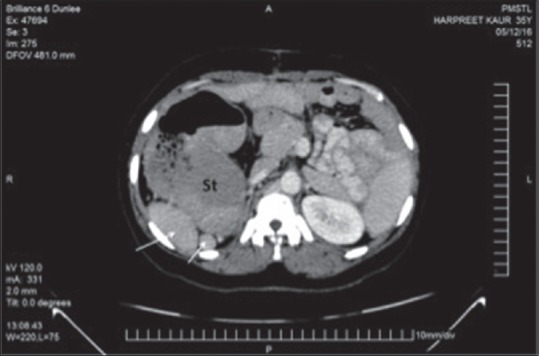

位置异常是一种罕见的结构缺陷,约占总人口的0.01%。他们表现出多系统的结构缺陷,主要涉及心血管、呼吸和胃肠道系统。存在多脾的位置异常被称为左心房异构体,其解剖和结构与脾不全的对应位置(右心房异构体)不同。在这个病例报告中,我们提出了一个成人病例的位置模糊异常是偶然诊断在腹腔镜胆囊切除术。患者肝左叶肿大,右侧多发脾,小肠和大肠旋转不良,下腔静脉中断伴奇静脉延续,双侧双叶肺。结论是,位置模糊情况的变化是不同的,单一的描述是不可能的。在手术和侵入性干预之前,利用成像方式揭示这些变异是至关重要的,以防止可能的风险和并发症。

Situs anomalies are rare structural defects affecting 0.01% of general population. They present with multisystem structural defects mostly involving cardiovascular, respiratory and GI systems. Situs abnormality with presence of multiple spleen is termed as left atrial isomerism with anatomical and structural differences to its countertype situs ambiguous with asplenia (right atrial isomerism). In this case report, we present an adult case of situs ambiguous anomaly which was diagnosed incidentally during laparoscopic cholecystectomy. The patient had enlarged left lobe of liver, multiple splenules on right side, malrotated small and large gut, interrupted inferior vena cava with azygos continuation, and bilateral bilobed lungs. It is concluded that variations in situs ambiguous cases differ and a single description is not possible. It is crucial to reveal these variations by using imaging modalities and being aware of them prior to surgery and invasive intervention to prevents the possible risks and complications.